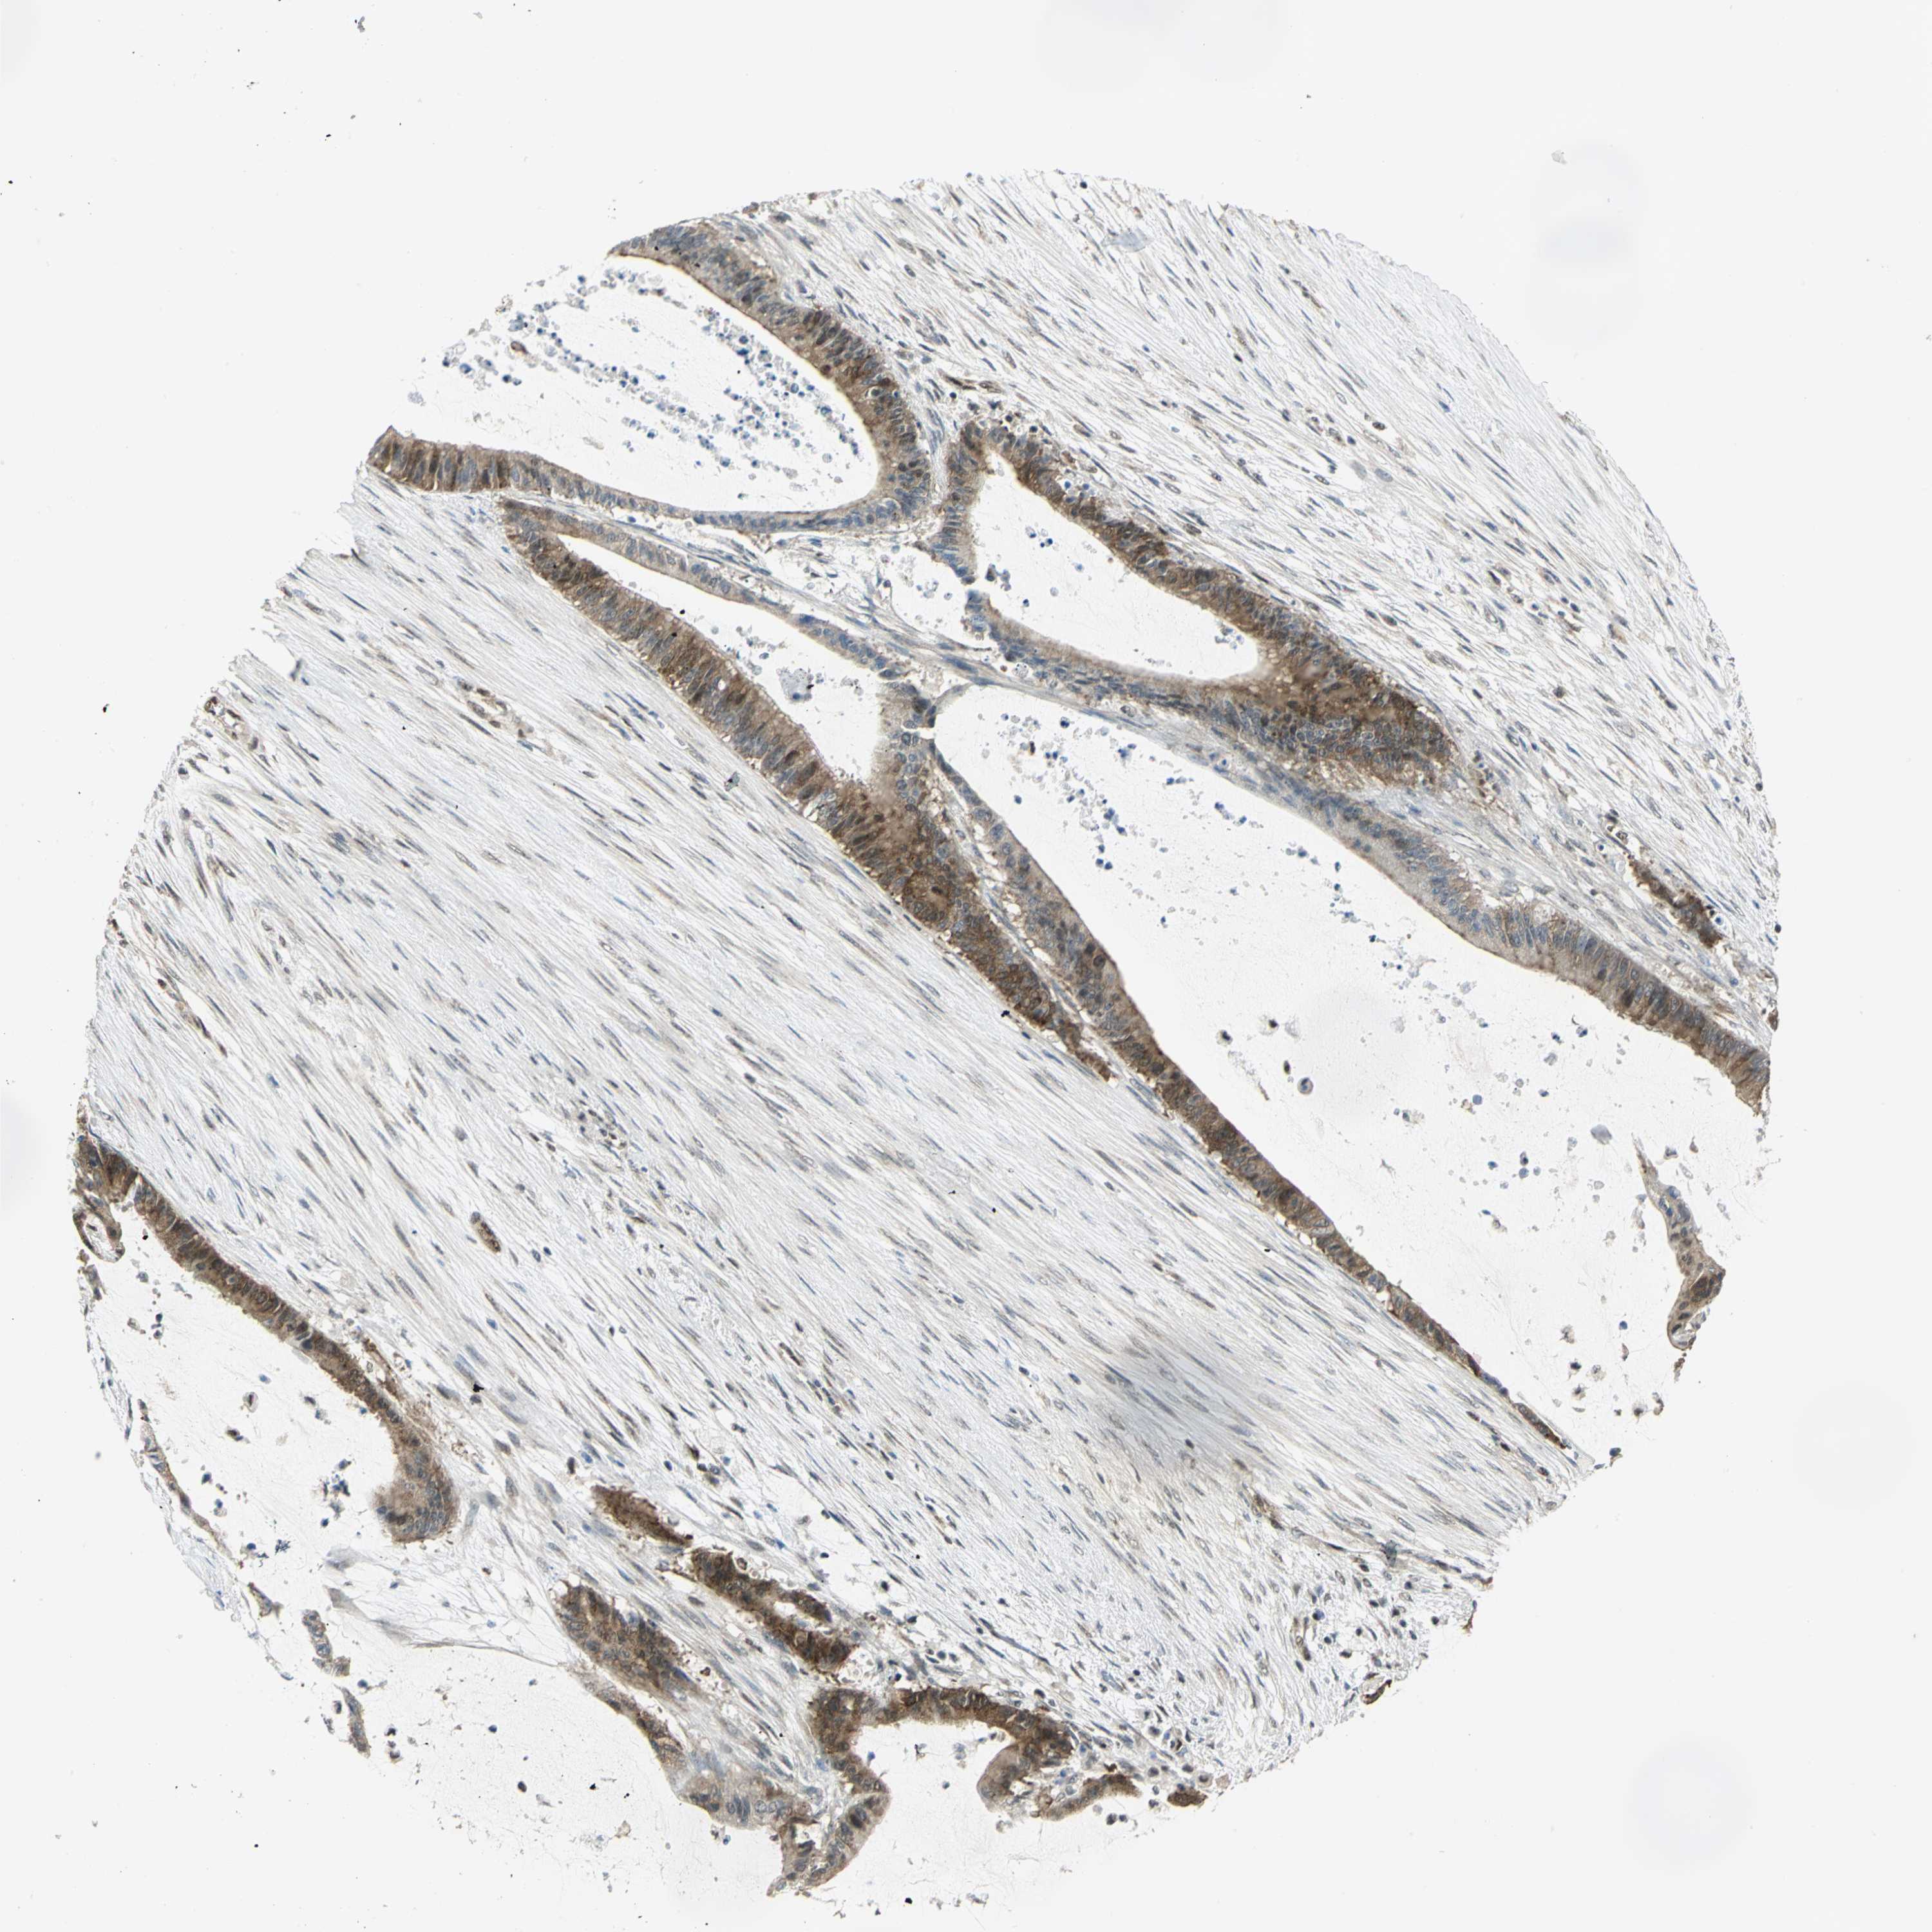

LIVER CANCER - Protein expressioni

A mouse-over function shows sample information and annotation data. Click on an image to view it in a full screen mode. Samples can be filtered based on level of antibody staining by selecting one or several of the following categories: high, medium, low and not detected. The assay and annotation is described here.

Note that samples used for immunohistochemistry by the Human Protein Atlas do not correspond to samples in the TCGA dataset.

Antibody stainingi

Antibody staining in the annotated cell types in the current human tissue is reported as not detected, low, medium, or high, based on conventional immunohistochemistry profiling in selected tissues. This score is based on the combination of the staining intensity and fraction of stained cells.

Each image is clickable and will lead to virtual microscopy that enables deeper exploration of all samples and also displays staining intensity scores, fraction scores and subcellular localization as well as patient and tissue information for each sample.

Antibody HPA020043

Antibody CAB005868

Staining

High

Medium

Low

Not detected

Intensity

Strong

Moderate

Weak

Negative

Quantity

>75%

75%-25%

<25%

None

Location

Nuclear

Cytoplasmic/membranous

Cytoplasmic/membranous,nuclear

Carcinoma, Hepatocellular, NOS

Cholangiocarcinoma